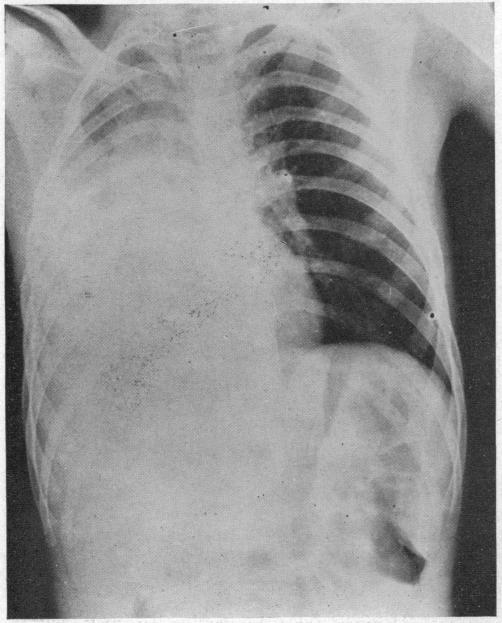

ACUTE MASSIVE COLLAPSE OF THE LUNGS: A DISCUSSION OF ITS MECHANISM AND OF ITS RELATION TO FOREIGN BODIES IN THE BRONCHI AND POST-OPERATIVE COMPLICATIONS.

Ann Surg. 1925 Sep;82(3):364-89. doi: 10.1097/00000658-192509010-00005.